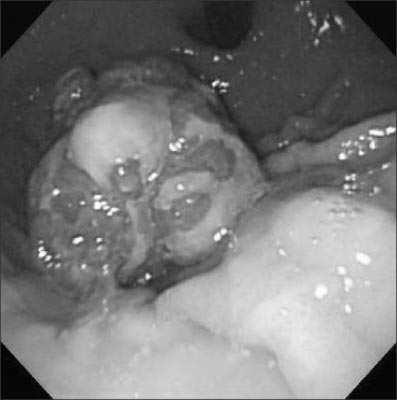

On exploratory laparotomy, a 4.5×3.5 cm sized exophytic and endophytic mass was found at the lesser curvature of the upper gastric body. A small bowel diverticulum was also found at the distal ileum and the diverticulum showed no signs of complication. Wedge resection of the stomach and diverticulectomy were performed. Histopathologically the gastric polypoid mass was confirmed to be a mature cystic teratoma (

Fig. 2,

Fig. 2Gross finding shows 4.2×3.4×3.0 cm sized multi-lobulated mass, with both exo- and endophytic growth.